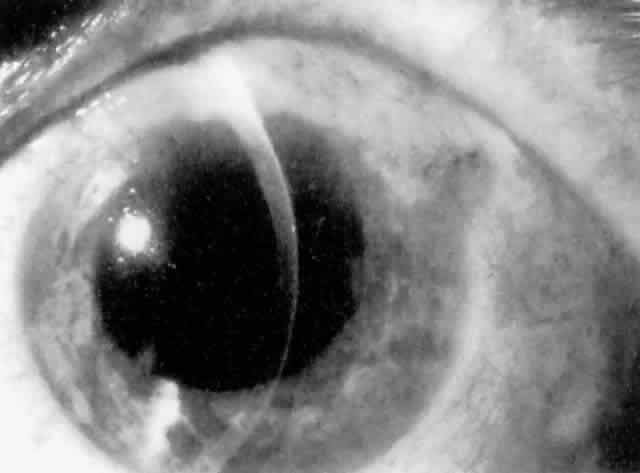

MANAGEMENT. Laser peripheral iridectomy quickly resolves pupillary block (Figs. 6 and 7). Because of inflammation and iridocorneal contact peripherally, this procedure may be difficult to accomplish. If the view is inadequate or a laser is not available, pupillary dilation with phenylephrine will in some cases relieve pupillary block (Figs. 8 and 9). Ultimately the patient will need a laser peripheral iridectomy. If peripheral anterior synechiae have formed or the IOP elevation persists after relief of the pupillary block, the patient will require management similar to that used in chronic angle-closure glaucoma.

Fig. 6. Pupillary block with iris bombé around haptics of anterior chamber lens implant, resulting in elevated intraocular pressure.

Fig. 7. Resolution of pupillary block after laser peripheral iridectomy.